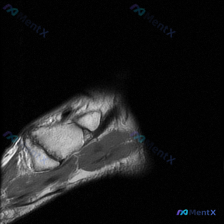

整理了一份很有警示意义的腕部MRI读片病例,分享一下我的分析思路,大家可以一起讨论。 病例影像基本信息 这是一张手腕关节的MRI T1加权序列冠状位图像,初始观察描述提示为「软骨异常」,我们来看看实际影像发现。 影像基础观察 1. 骨骼结构:图像清晰显示头状骨、钩骨、三角骨等腕骨,以及掌骨基底、桡尺...